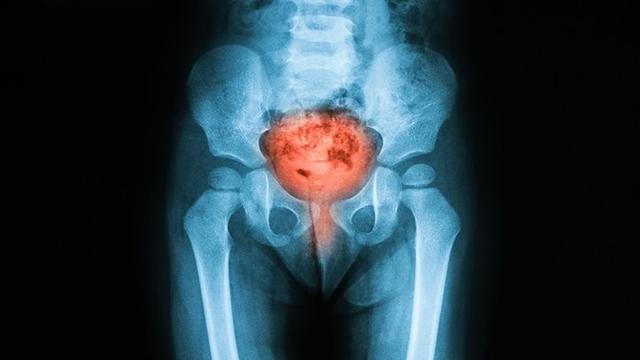

对不起,放错图了。咳咳……

应该是这张